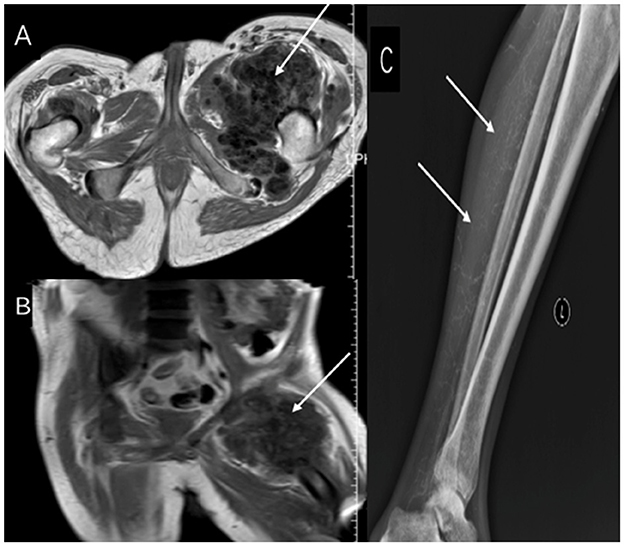

Upon admission, laboratory tests revealed elevated parathyroid hormone (PTH, 650.30 pg/ml) and serum phosphorus (2.85 mmol/L), indicating secondary hyperparathyroidism. Imaging showed metastatic calcifications in the sacral region and left proximal femur (Figures 1A, B), highly suggestive of calcific CUA. Given his medical history, the patient underwent total parathyroidectomy with autotransplantation. Postoperatively, iPTH decreased to 35.15 pg/ml, and serum calcium stabilized at 1.82 mmol/L, although hyperphosphatemia persisted (serum phosphorus 2.66 mmol/L).

Figure 1

Serial imaging demonstrating calcification progression. (A, B) Pre-parathyroidectomy MRI shows sacrococcygeal and left femoral calcifications with perihippocampal edema (arrows). (C, D) Postoperative (19 months) CT reveals new spinal (C7-T1), thoracoabdominopelvic calcifications, and widespread tumoral calcinosis (shoulders, ribs, spine, femur, sacrum) with soft tissue calcification (arrows).

Eighteen months after thyroid surgery, follow-up imaging revealed new extensive metastatic calcifications involving the shoulders, ribs, spine, femur, and sacrum (Figures 1C, D). In March 2023, the patient presented with worsening bilateral ankle ulcers, including a 15 cm stellate calciphylactic skin lesion (Figure 2A). Wound secretion cultures were negative, ruling out necrotizing soft tissue infection. Inflammatory markers were significantly elevated: white blood cell count 11.62 × 109/L, high-sensitivity CRP 279.88 mg/L, PCT 14.88 ng/ml, and persistent hyperphosphatemia (serum phosphorus 2.19 mmol/L). Given the severity of his condition, the patient started intravenous STS therapy on March 29, 2023, following a stepwise dose-escalation protocol: starting at 3.5 g daily, increasing every other day to 5, 7, 8 g, and ultimately 10 g daily. The patient completed a 2-week course of treatment. In addition to STS, the patient received piperacillin-tazobactam for infection, Dan Shen injection for microcirculatory improvement, sevelamer for phosphorus control, esomeprazole for gastric protection, and optimized dialysis (using low-calcium dialysate). After the first STS course, CRP decreased by 77.3% (from 279.88 to 63.63 mg/L), and the ulcer area reduced by 42% (Figure 2B).

Figure 3

(A, B) MRI after STS therapy shows persistent sacrococcygeal/femoral calcifications (arrows), and (C) DR reveals new deposits in the knee region (arrow).